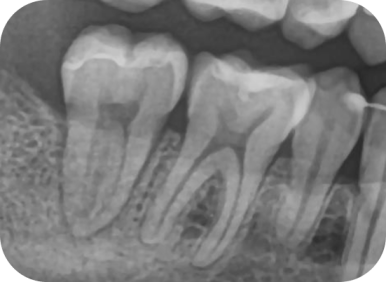

✅ 실제 치료 케이스 2: 우측 어금니 #47 C-shape canal

- 환자 증상: 어금니 통증, 씹기 어려움

- 진단: 크랙으로 인한 치수염, 신경치료 결정

🔬 MTA 실러 + GP cone 이용한 충전

| 전 | 후 |

→ C형 근관 특유의 얇은 통로까지 완벽하게 충전

→ 치료 후 통증 소실, 크라운 수복 완료